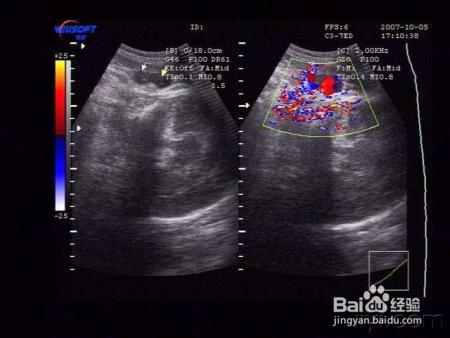

吴琪琪现在孕26周,已经度过半个孕期的她心情十分好,每天都要坚持走1.5w~2w步。用她自己的话说,一方面是要给胎儿足够的锻炼,避免胎儿过大;另一方面也是为了自己产后身材恢复打下基础。可是,当去做了孕中期的大排畸之后,医生很严肃地跟她说:“胎儿脐带绕颈三周,一定要特别注意,胎动异常要及时要医院就诊。”